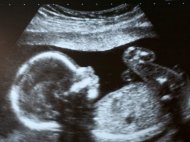

Врачи случайно обнаружили в утробе 92-летней жительницы Чили мумифицировавшийся плод.

Пожилая женщина, имя которой не называется, неудачно упала и обратилась в больницу за медицинской помощью с жалобами на боли в животе.

Во время обследования выяснилось, что в животе женщины находится плод, пишет Хроника.инфо со ссылкой на napensii.ua.

По заключению врачей беременность женщины замерла на 30-й неделе полвека назад. Женщина сказала медикам, что не знала тогда о своей беременности.

Причину гибели плода врачи не установили. Они решили не удалять плод, так как операция может навредить пациентке. До падения женщина никаких проблем со здоровьем не испытывала. После проведенного в госпитале лечения, бабушка выписалась домой.